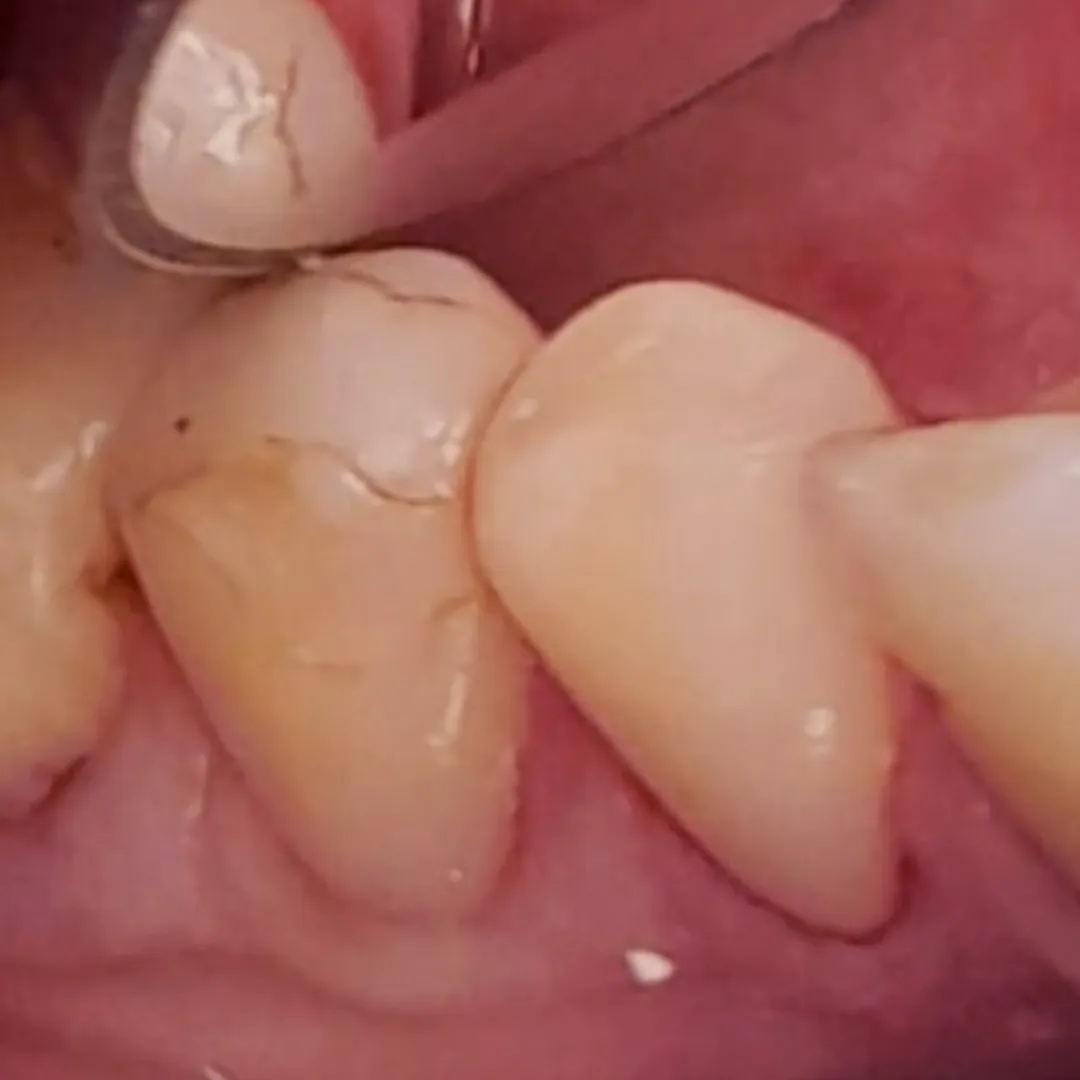

Пациентка обратилась в «Стоматологию Комфорта» с жалобой на отсутствие зубов верхней челюсти. По результатам обследования врач стоматолог-ортопед, хирург-имплантолог Мельников Алексей Владимирович назначил имплантацию по методу «all-on-4». По истечении 6 месяцев после операции проведено обслуживание условно-съёмного протеза. Также врач начал восстановление нижней челюсти коронками в комбинации с бюгельный протезом.

- восстановление нижней челюсти коронками в комбинации с бюгельным протезом.